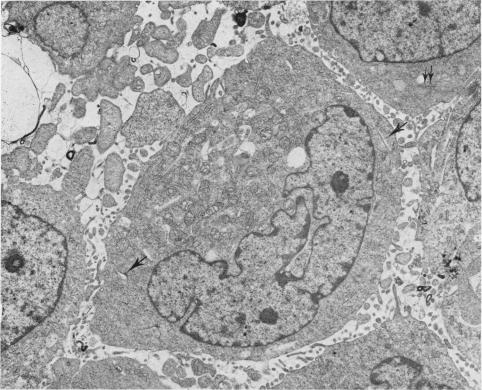

Fig. 4.

Fig. 4